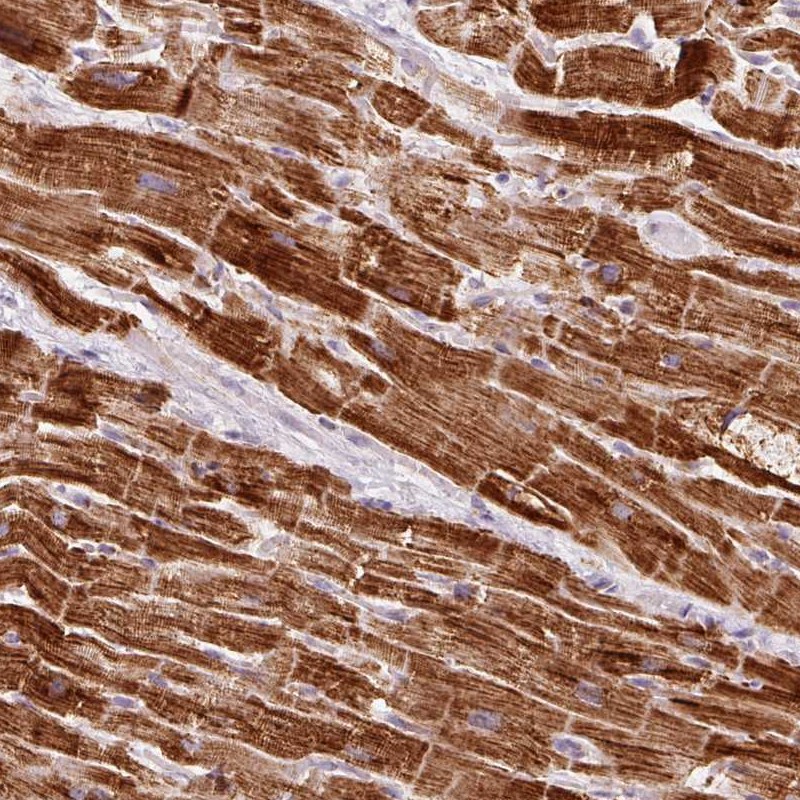

Immunohistochemistry analysis in human heart muscle and pancreas tissues using Anti-NDUFB4 antibody. Corresponding NDUFB4 RNA-seq data are presented for the same tissues.